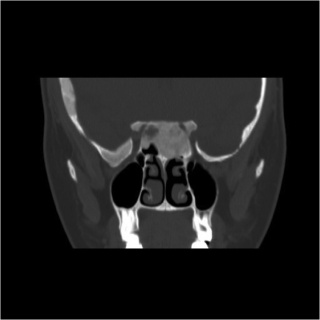

Diagnostic procedures

Fibrous dysplasia was initially studied using plain X-rays, and its characteristic mottled, sclerotic appearance described as resembling “ground-glass.” Today, lesions may be well characterized on computed tomography. The radiographic features vary based on the proportion of normal, mineralized bone to fibrous tissue in any given lesion. Early in the disease course, cystic and sclerotic areas are noted. As dysplasia progresses, a heterogeneous “pagetoid” pattern of radiolucent and radiopaque areas is seen, reflecting regions of fibrous stroma and opaque, osseous changes, respectively. [11][4] Typically, fibrous dysplasia has smooth cortical margins and no soft tissue involvement. [3][11][2] On MRI, lesions are low to isointense on T1 and T2-weighted images, and demonstrate moderate enhancement with gadolinium. [5][4][1]

Radiographic optic nerve bony encasement is exceedingly common in craniofacial fibrous dysplasia, and may approach rates as high as 50-90% of patients. [14][21] The relationship between optic canal stenosis and visual compromise is uncertain, however, as large studies have demonstrated that the majority of patients with completely encased nerves remain asymptomatic without evidence of optic neuropathy. (Figures 1 and 2) [10][14][16]